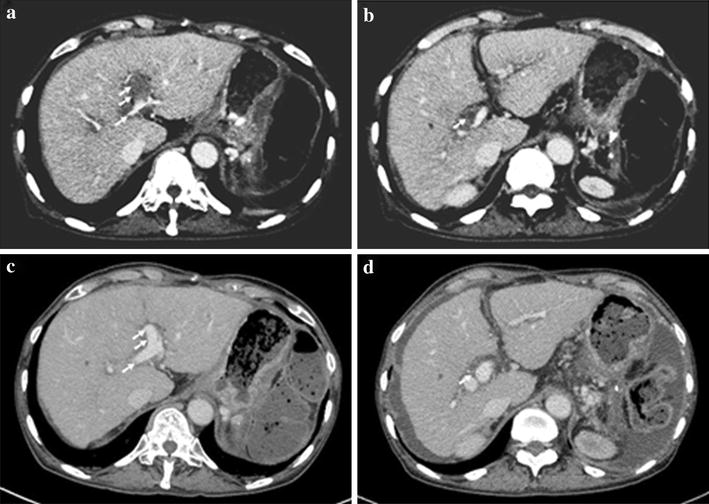

JCM Free FullText Primary CatheterDirected Thrombolysis for Porto Catheter Directed Thrombolysis For Portal Vein Thrombosis  Diagnosis, management, and endpoints for future clinical studies. Portal vein thrombosis most commonly occurs as a complication of liver cirrhosis and can result in worsening symptoms of. Web cdt was performed with infusion catheters placed via percutaneous transhepatic (pth) and/or transjugular intrahepatic (tj). Catheter Directed Thrombolysis For Portal Vein Thrombosis.